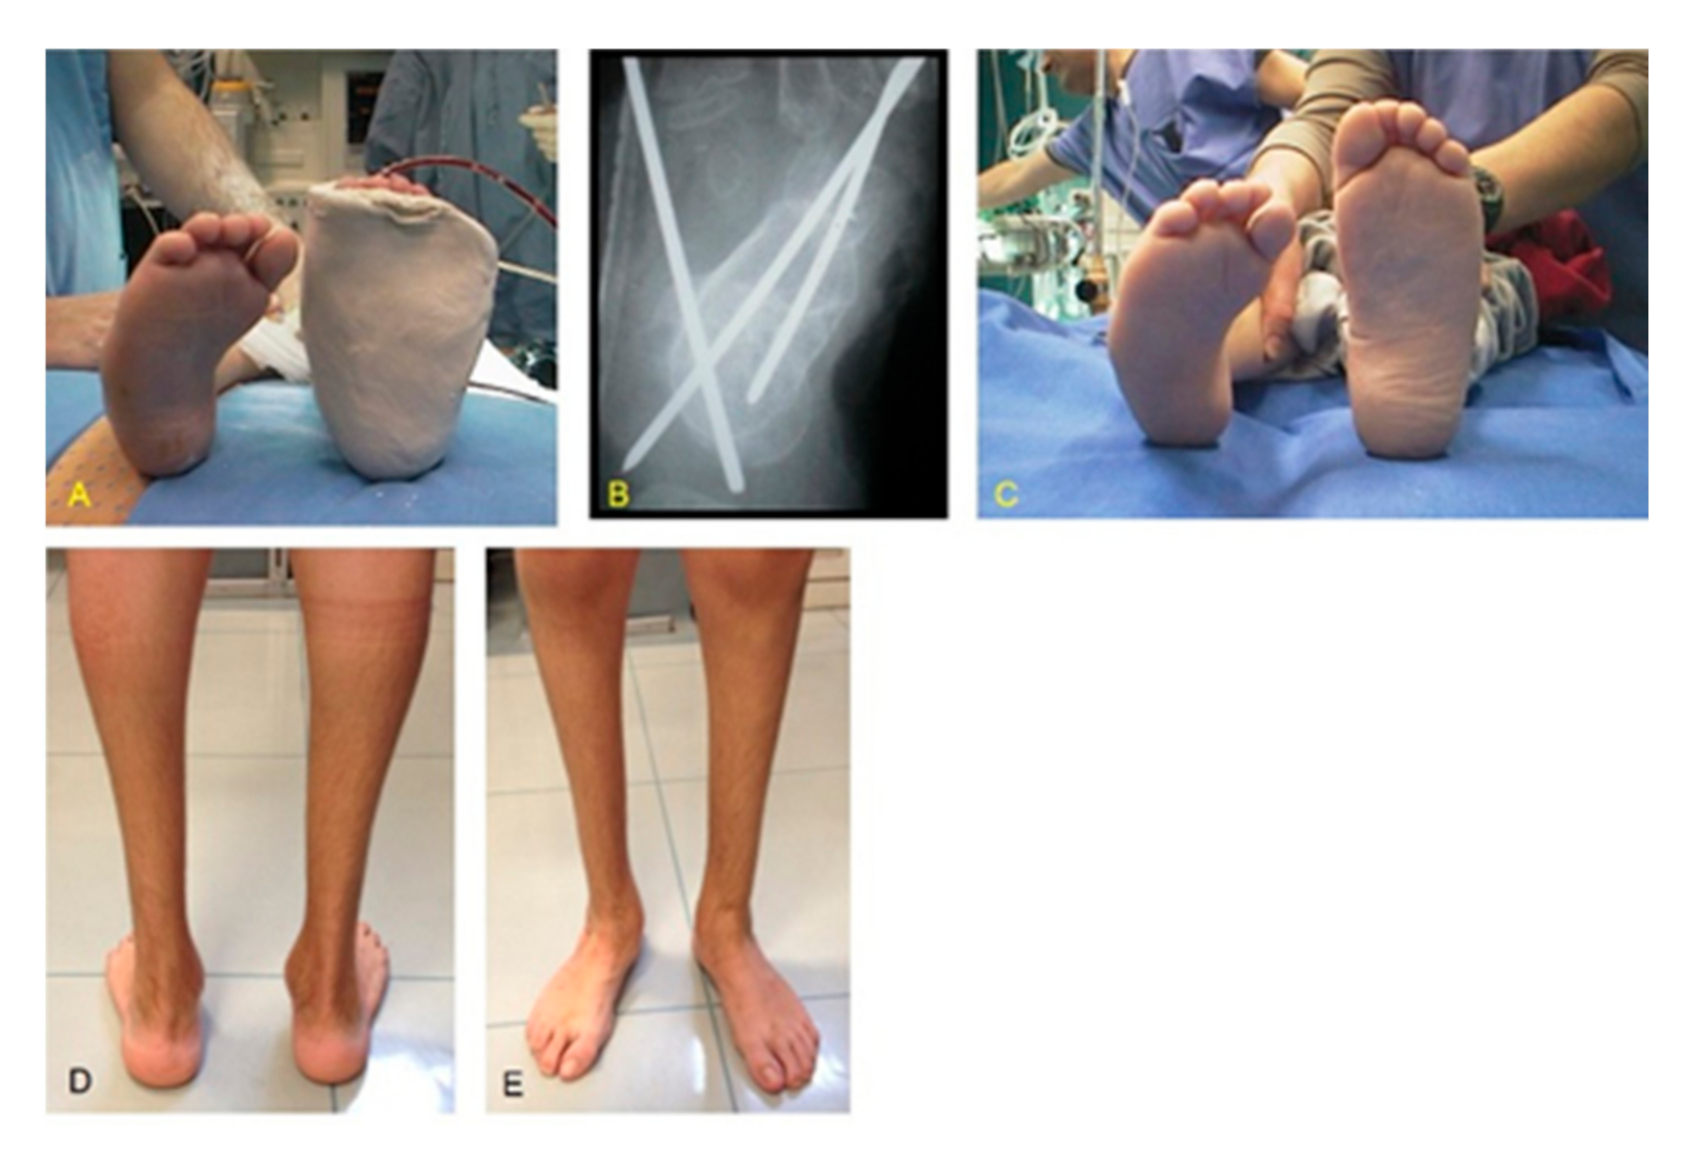

Figure 3. Same patient as shown in Figure 1: (A) postoperative cast immobilization after relapse surgery (ATL, PR, PM, tibialis anterior transfer, and cuboid osteotomy); (B) X-ray showing correction of the talocalcaneal relationship and K-wires fixation; (C) clinical aspect of both feet at the time of relapse surgery of CF right; (D) clinical results at a 18.2-year of follow-up with good alignment and correction of the hind foot; (E) frontal view showing correction of all CF components.